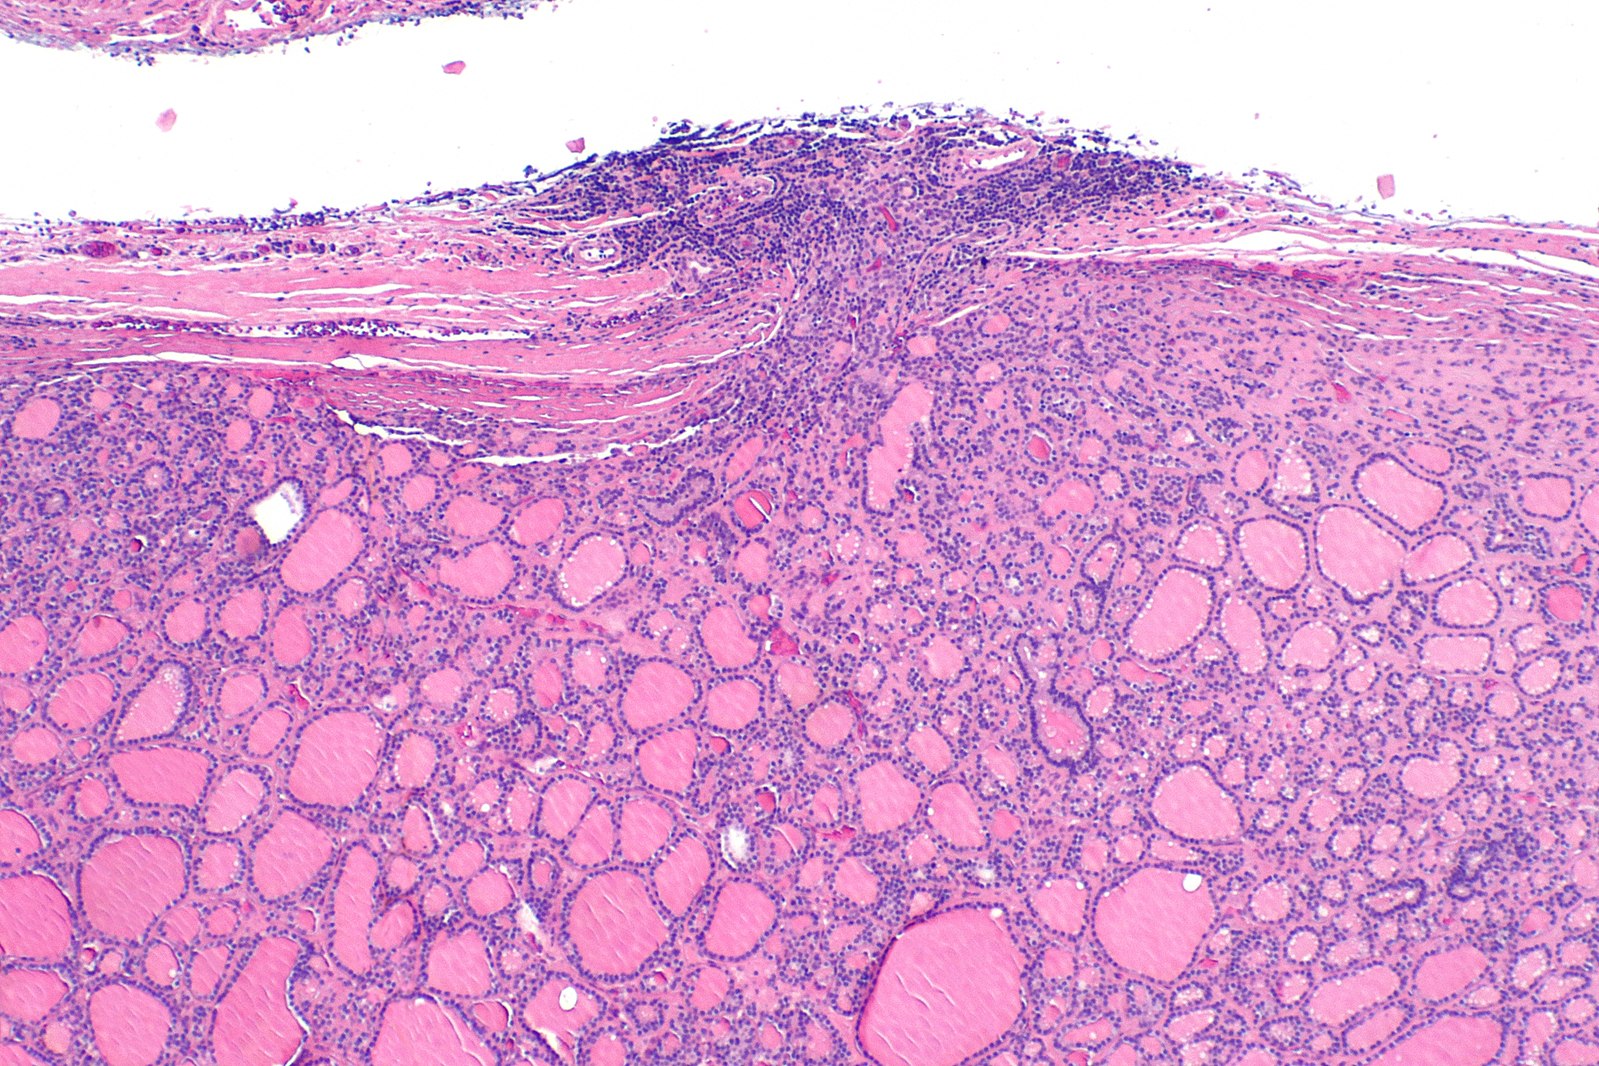

Follicular Thyroid Cancer

Follicular thyroid carcinoma that is more aggressive in terms of malignancy intensity. It is rare and contributes to around fifteen percent of all carcinomas of thyroid. This cancer spreads to the lymph nodes in the neck and then other distant organs like lungs and bones and the initial symptoms include – changes in voice, pain in neck, increased hoarseness and difficulty in swallowing.

The tumor is encapsulated

Usually hematogenous route of spread

Distant metastasis to occiput

Insufficient Iodine intake, irradiation exposure and older age

- Occurs between ages – 40 through sixty

- Females more common than males by 3 to 1 ratio

- Prognosis (the likely course of a medical condition) directly associated to tumor size [less than one cm (3/8 inch)]

- Related to radiation exposure on rare occasions

- Spread to lymph nodes is not common (~ twelve percent)

- Cancer spread to lungs or bones is not common, but definitely more common in comparison to the papillary cancer

- Curative possibility is high (near ninety five percent for small lesions in young patients), reduces with advanced age

- Invasion into the circulatory system (veins and arteries) within the endocrine gland (the thyroid gland) is common

- Minimally invasive follicular carcinoma: very low long-term mortality

- Widely invasive: fifty percent long term mortality

- Poor prognostic characteristics – the size of the tumor (abnormal mass of tissue) size greater than four cm, cancer that has spread from the original tumor to distant lymph nodes – distant metastases, forty-five years of age or greater, large size, extensive vascular invasion (blood and/or lymph vessel invasion (LBVI), extrathyroidal extension (extension of the primary tumor outside of the thyroid capsule and invasion into the surrounding structures)

[3]Image credit: https://commons.wikimedia.org/wiki/File:Follicular_thyroid_carcinoma_--_low_mag.jpg